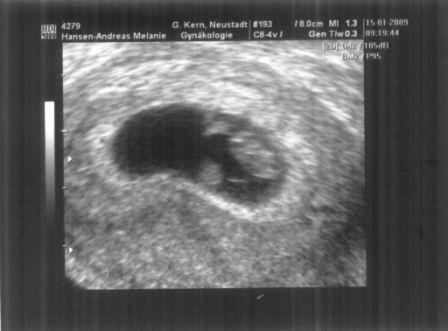

Hier das erste Bild unseres Böhnchens. Das war SSW 6+1. Oder wie mein

Bruder darauf sagte: "Oh Melle, ich dachte du hast einen Spunk verschluckt.

" (Ein Spunk ist ein kleines dänisches Lakritzpastillchen. Siehe 2. Bild.